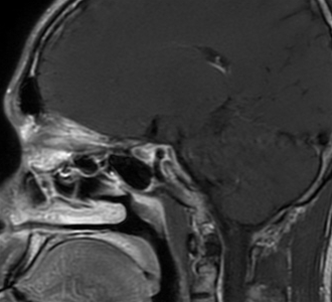

术后影像

术后CT磨除范围

术后颅骨表面重建